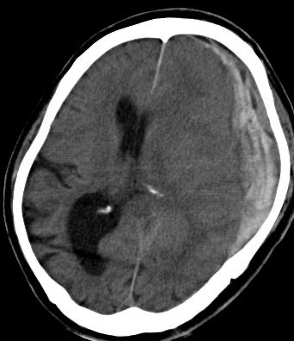

脳内出血

脳内出血は脳卒中のなかで、脳梗塞についで多い疾患で、出血量の少ない症例は保存的に加療しますが、出血量が30mlを越える症例については、機能的予後改善を目指し、症例を選んで定位的血腫吸引除去術を行っています。下記のような出血症例も、全身麻酔は不要で、駒井式定位脳手術装置用いて手術を行っています。

術前(左被殻出血)

駒井式定位脳手術装置を用いて血腫を吸引している(局所麻酔下)

定位的血腫吸引術後 被殻出血は除去されている